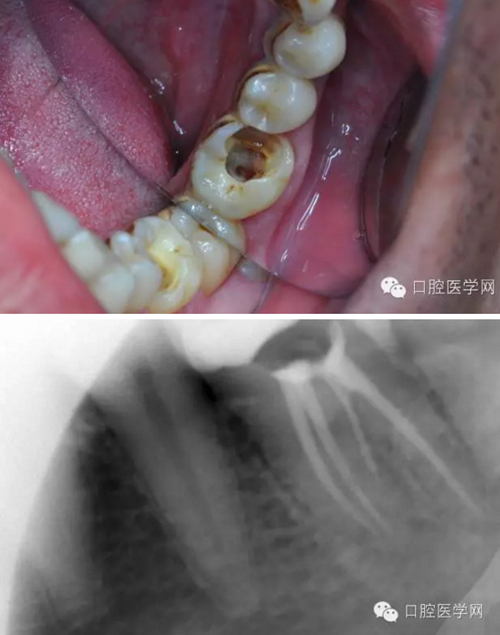

患者,肖某,男,32歲,#36慢性牙髓炎。遠(yuǎn)中舌根根尖1/3彎曲而且鈣化不通,我用盡辦法疏通了很久也沒到達(dá)WL,(我一直在幻想,要是有超聲系統(tǒng)該多好,可是現(xiàn)實很骨感,我們單位暫時還沒有超聲系統(tǒng)),后來我放棄了,最后的根充片顯示遠(yuǎn)中舌根充填物距根尖端2.84mm,屬于欠填范圍(根管內(nèi)充填物距根尖端2mm以上),其它三根根尖1/3鈣化相對沒那么嚴(yán)重,根充片顯示屬于恰填范圍(根管內(nèi)充填物距根尖端0.5~2mm)。歡迎網(wǎng)友們針對這個病例提出寶貴的建議!

9.png

10.png